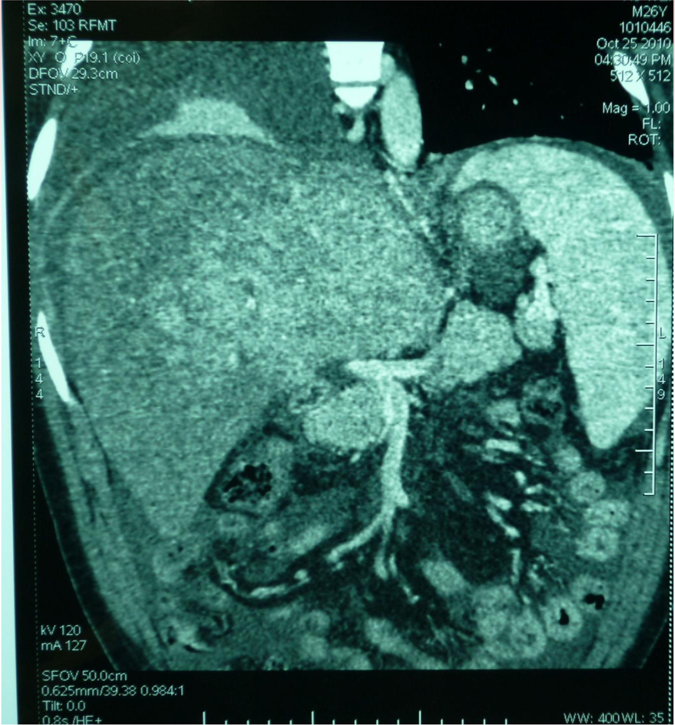

男性,26岁,因无明显原因出现腹胀纳差伴少尿一个月入院。

入院检查:强迫半卧位、巩膜黄染、腹部高度膨隆。双侧胸腔积液,大量腹水。

实验室检查:

总蛋白52.8g/L

白蛋白30.2g/L

谷丙转氨酶554u/L

谷草转氨酶378u/L

总胆红素74.9umol/L

直接胆红素18.51umol/L

尿素氮10.2mmol/L

低钠、低氯

肠房转流术

肠房转流术后,现在随访14年